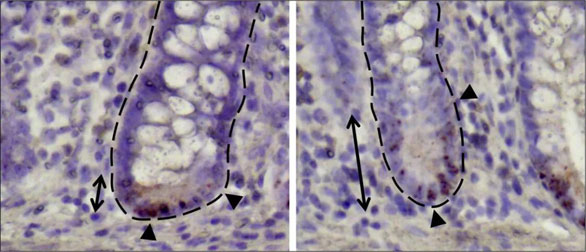

克羅恩病患者的小腸隱窩。資料來源:TUM

▲ 腸干細(xì)胞與潘氏細(xì)胞的相互作用

干細(xì)胞對于組織的維持和再生是必不可少的。腸道內(nèi)的腸干細(xì)胞與潘氏細(xì)胞混雜在一起。潘氏細(xì)胞負(fù)責(zé)局部免疫防御,并創(chuàng)造一個干細(xì)胞可以生長的環(huán)境,因此被稱為干細(xì)胞生態(tài)的守護(hù)者。

克羅恩病患者的潘氏細(xì)胞較少,而且功能受限。研究小組研究了潘氏細(xì)胞發(fā)生變化的原因,并試圖確定在這種情況下干細(xì)胞代謝的重要性。除動物實(shí)驗(yàn)外,研究人員還分析了克羅恩病患者的腸道活組織切片,對干細(xì)胞生態(tài)位進(jìn)行了細(xì)致入微的描述。6個月后,患者的腸道再次接受內(nèi)窺鏡檢查,重點(diǎn)尋找炎癥跡象。